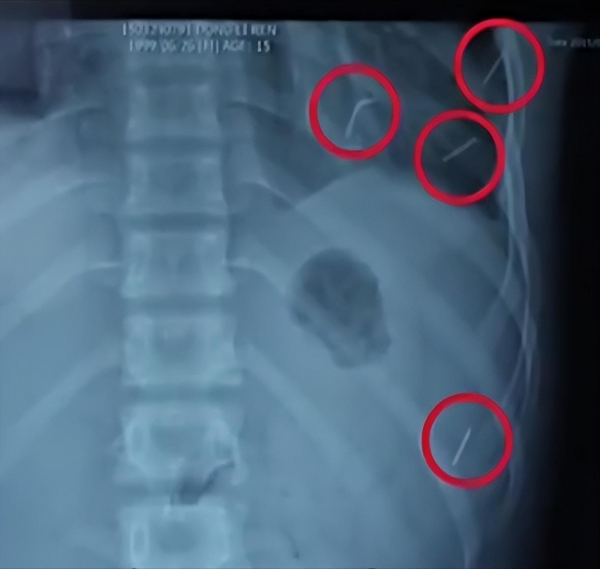

在董立仁的体内,有4根不一样长的细针,3根位于董立仁的胸部,1根位于腹部,不仅如此,3根位于胸部的细针中,竟然有1根正好扎在了董立仁的心脏上。

此时要怎么取针,成了所有医生心中的疑惑,超声科的医生在看过董立仁的状况之后,发现这枚针在心包上面扎着董立仁的心脏,

但是还没等医生松口气,他们很快发现了另一个严峻的问题,当血水褪去之后,他们发现这枚针已经扎到心脏左室的后侧壁里面了,露在外面的针只剩下了1公分长,不仅如此,随着银针的深入,此时的心脏还在不停的往外渗血。

拍片的时候,医生以为这枚针只是扎在了心包上面,却没想到这枚针已经深深的扎在了心脏里面,甚至直接扎到了左心室里。

当看到那根针的时候,医生还是忍不住惊呼,这根针足足有4厘米长。

正常人的心脏和拳头差不多大,一般有5厘米长,而幸好这根针是斜着插入心脏的,这才让董立仁逃过一劫。

此时的医生看着董立仁体内取出来的两根针,这两根针颜色发黑,长的有5厘米,短的则有2厘米,并且尖端锋利,这些针是哪里来的呢?

刚开始很多人都以为这只是普通的缝纫针,但是当和真的缝衣针进行对比的时候,却发现董立仁体内的针根本和这个不同,缝衣针的表面光滑,并且尖端很规整,但是董立仁体内的针颜色发黑并且尖端是不规则的横截面,跟普通的绣花针不太一样,所以可以断定,这些根本就不是缝衣服的针。